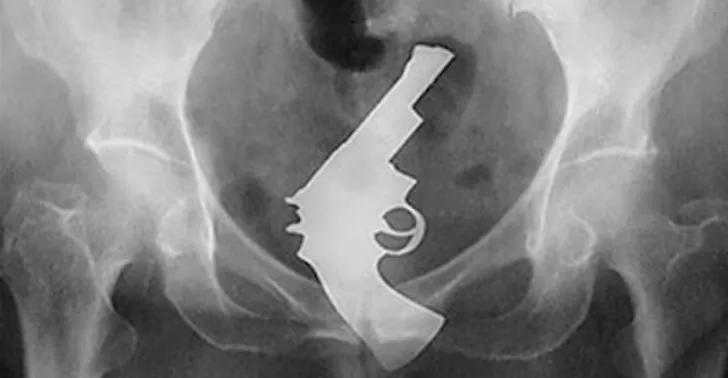

Anders vergaat het de horden die colaflessen, deurkrukken, eierwekkers of biljartballen in anus of vagina steken en de huisraad er niet meer uitkrijgen. Dit is doorgaans niet direct levensbedreigend, maar zeker op termijn wel problematisch. Lang wachten met hulp zoeken kan tot levensgevaarlijke complicaties leiden.

Met de parafernalia die artsen jaarlijks uit mensenlichamen opdiepen, zou je een aardige bazaar kunnen inrichten. Het merendeel van de goederen hoort thuis in de categorie Rectaal Gevonden Voorwerpen.